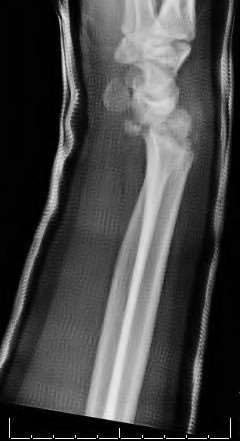

A 35-year-old woman reports wrist pain after a fall onto an outstretched hand. On exam, she has focal tenderness over the wrist snuffbox. A radiograph and CT image are shown in Figures A and B. What is the proper treatment of her injury?